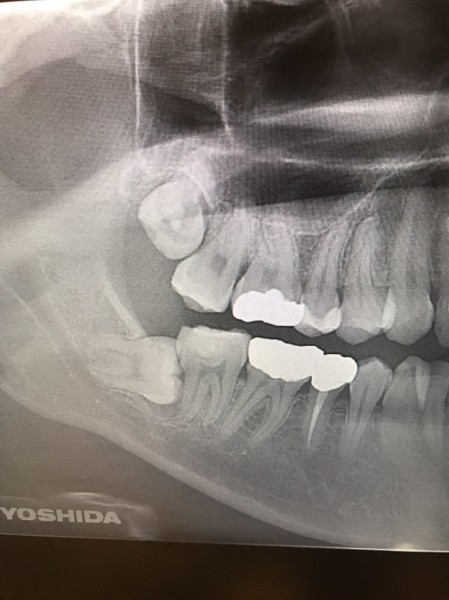

前医でインプラントの埋入角度が悪く、インプラント周囲炎になってしまった患者様の症例です。

インプラントが虫歯になることはありませんが、インプラント周囲炎というインプラントの歯周病にはなります。

インプラント周囲炎の主な原因は汚れ(菌)と力です。このように斜めに埋入されているインプラントは、真っ直ぐ埋入されているものに比べて汚れも溜まりやすく、噛む力も斜めにかかってしまうため、インプラント周囲炎になるリスクが大幅に高くなります。

この患者様は内側の骨が大幅に溶けてしまっていたので、前のインプラントを撤去して、骨を再生させると同時にインプラントを正しい位置と角度で埋入し直しました。溶けてしまっていた骨が治っていることもレントゲンでご確認いただけるかと思います。

インプラントは「どこの位置にどのような角度で入れるか」によって、一生使い続けられるかどうかの期待値が大きく異なります。値段だけを基準にクリニックを決めるのではなく、信用できる歯医医師と治療を進めることをお勧めします。